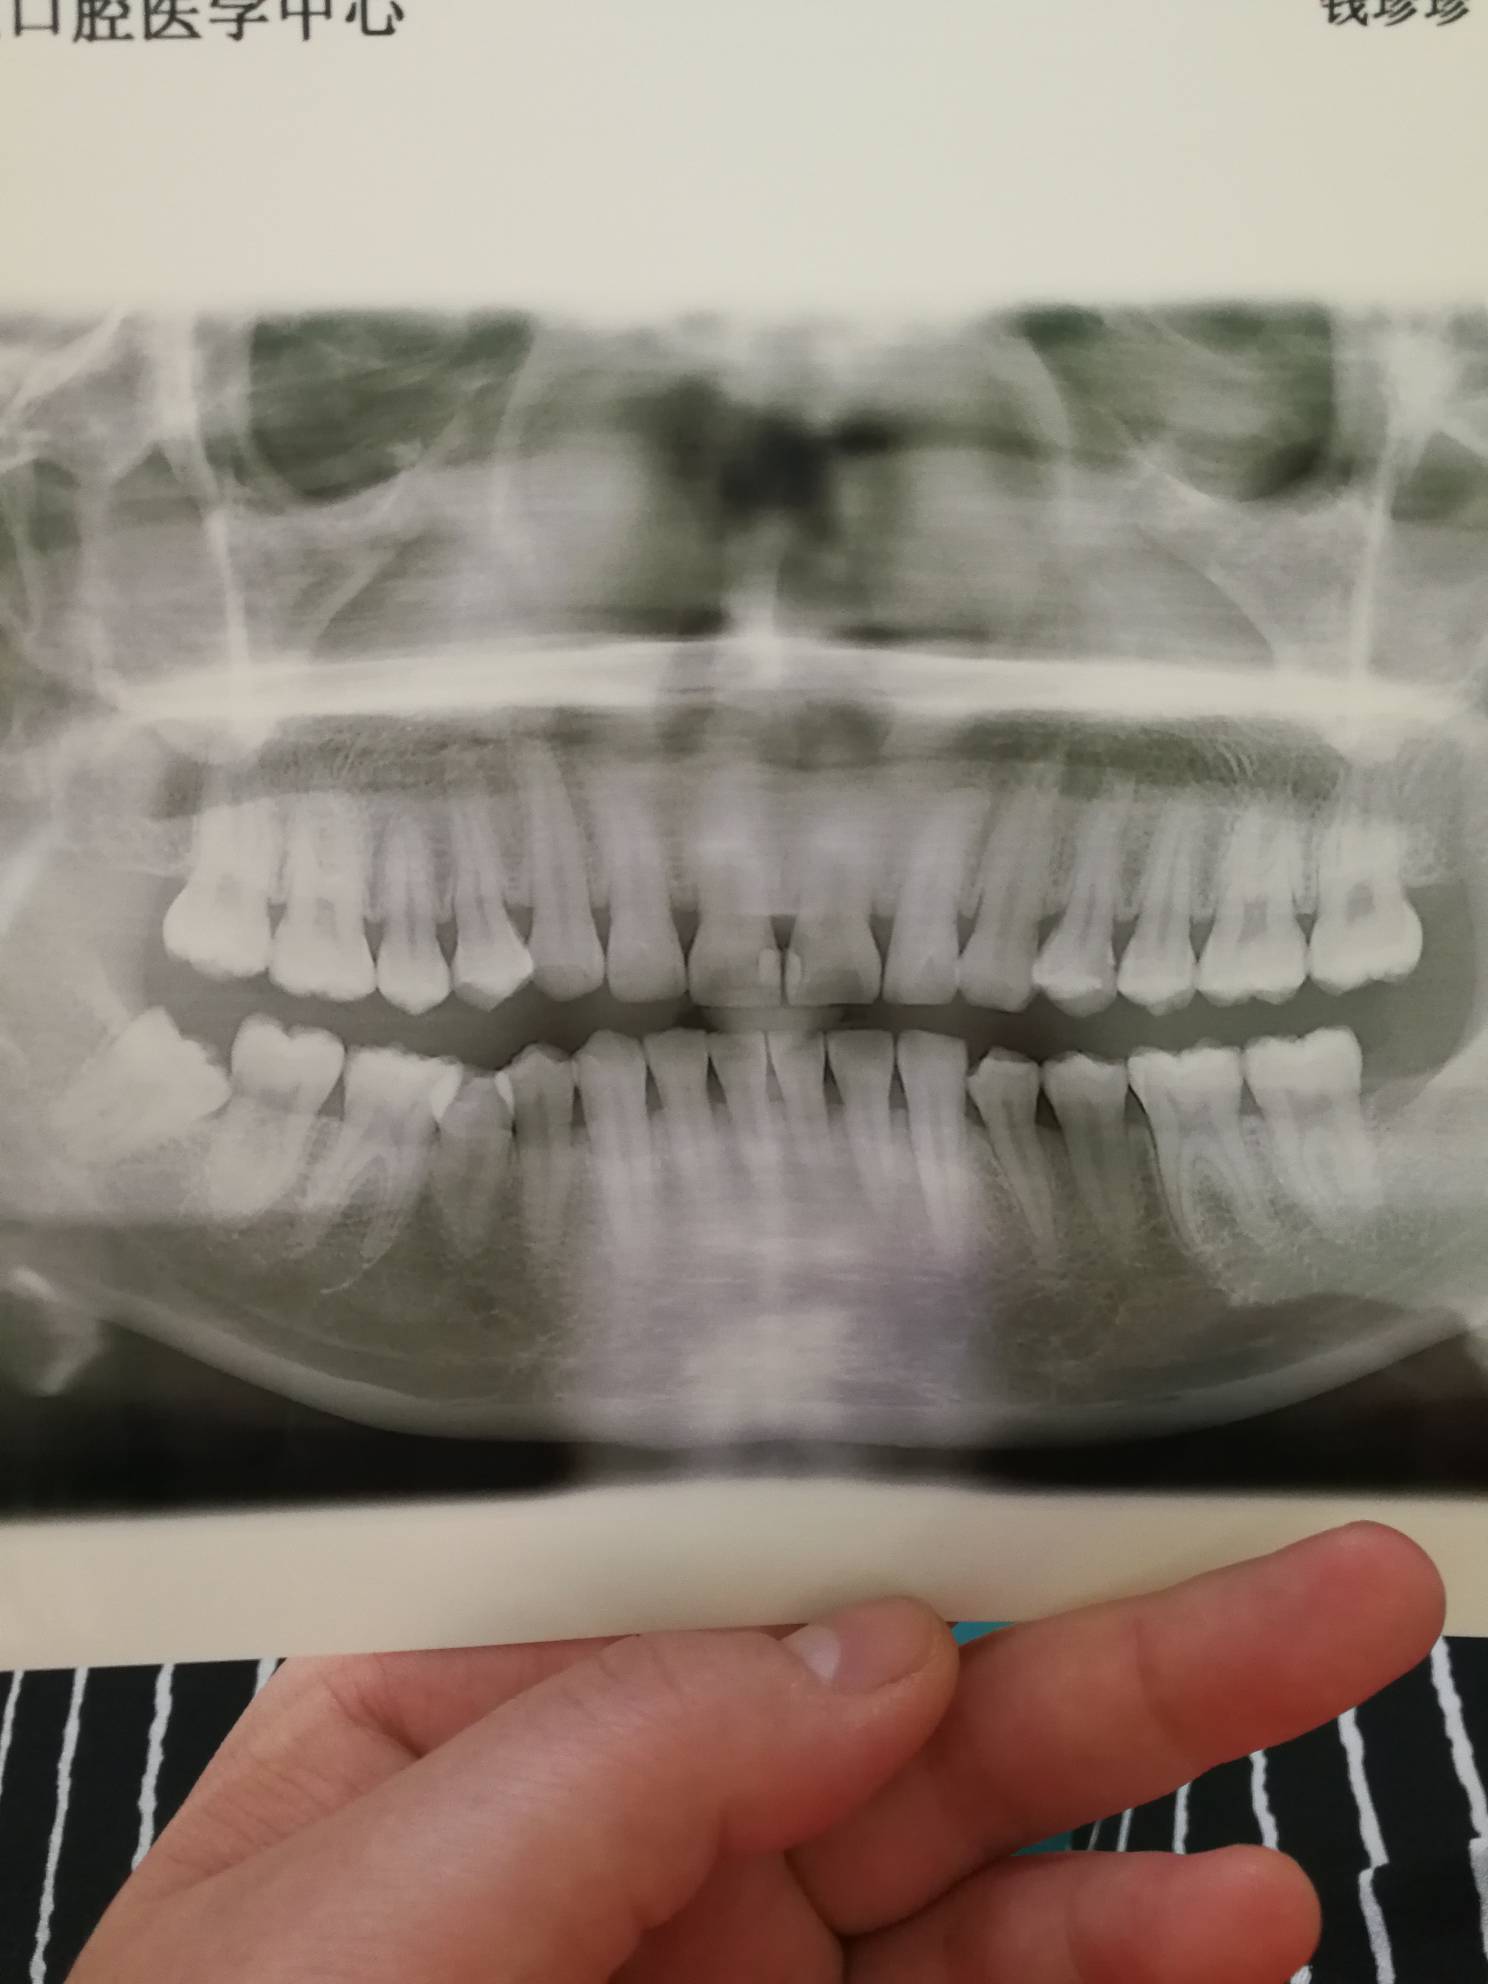

不拔,你会经常痛的,一上火就痛

如果有影响的话,就拔掉,我也长了一个,不过不影响,所以医生不建议拔掉

最里面那一颗

早晚也要拔